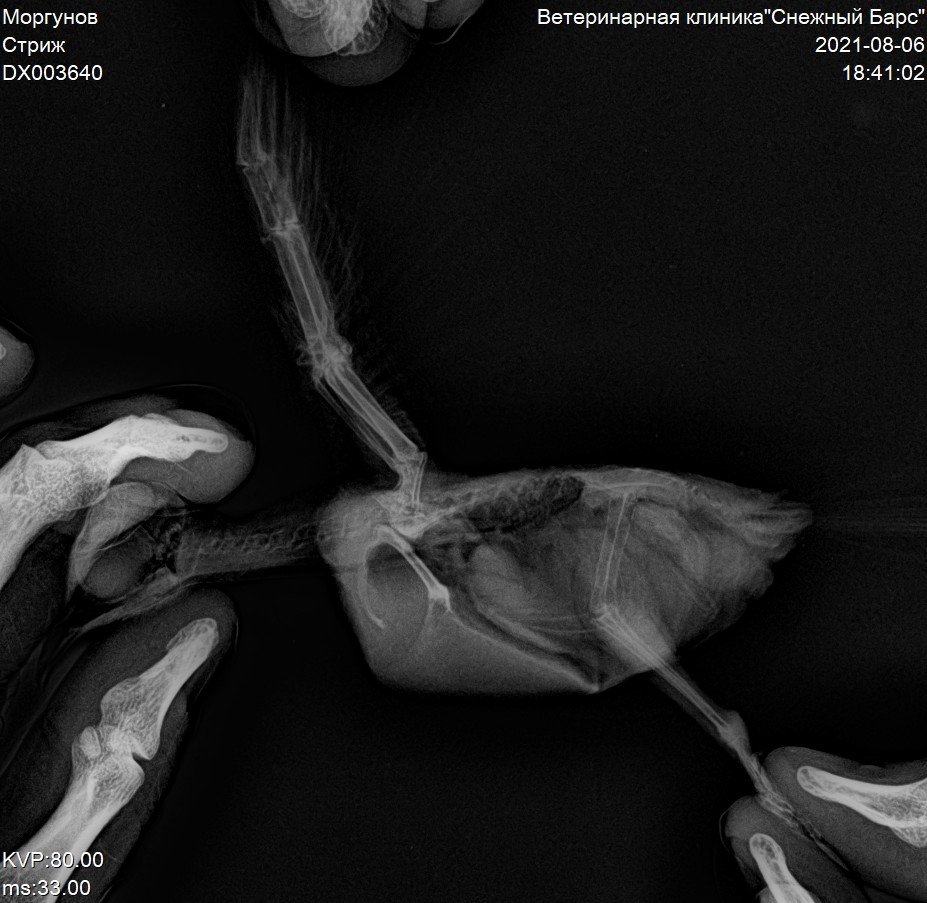

Рентгеновский снимок крыла птицы: анатомия и исследование